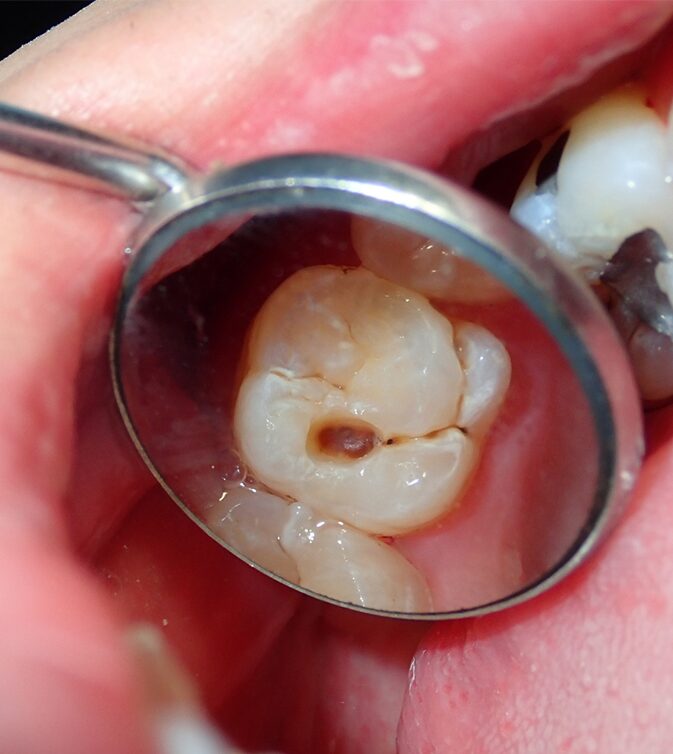

Tooth pain rarely resolves on its own. It often points to issues such as infection, decay, nerve damage, gum disease, or a cracked tooth. Without treatment, these problems tend to worsen.

- Treatment of cavities or cracked teeth